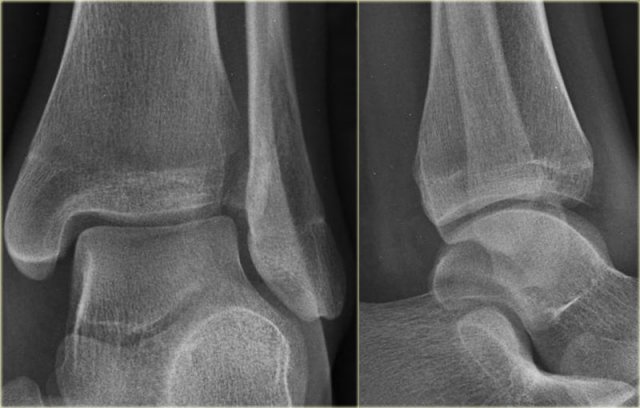

The images show an obvious Weber B fracture.

On the AP-view the linear lucency is the clue to a tertius fracture (red arrow).

It results from subtle malalignment of the fracture fragment.

Likewise in some cases malalignment can result in a linear density.